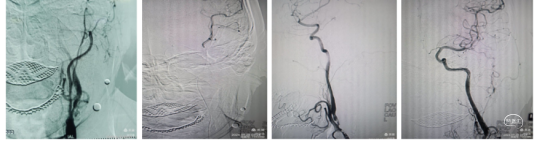

颈内动脉C1~C3血管迂曲呈u型、S型改变。血液滞留。泥鳅导丝、130cm西蒙导管、Neuron MAX长鞘同轴到达C1段到达S迂曲。

Nueron MAX长鞘高到位有助于起到近端阻断作用。引入6F通桥中间导管,打开中间导管尾部裸奔通过S型迂曲到C5段导管。尾部流血停止,说明到达狭窄或血栓部位,连接50mL注射器踹马桶抽吸,抽出30mL血液,见0.5Cm大小硬质血栓。下图所示

再次清理防止碎栓逃逸:抽吸至血流通畅,造影显示血管再通。但极重度狭窄,一抽见真情。

球囊扩张:微导丝携带微导管到达大脑中动脉M1段远端,沿微导丝输送2.5mm颅内白驹球囊扩张狭窄部位.缓慢打压,像拨秒表一样,1、2、3、4…1分钟1个大气压的速度充盈球囊至3-5个大气压。球囊充盈应该两段先充盈狭窄部位后充盈,保持3-5秒,缓慢泄压,这样防止形成夹层。